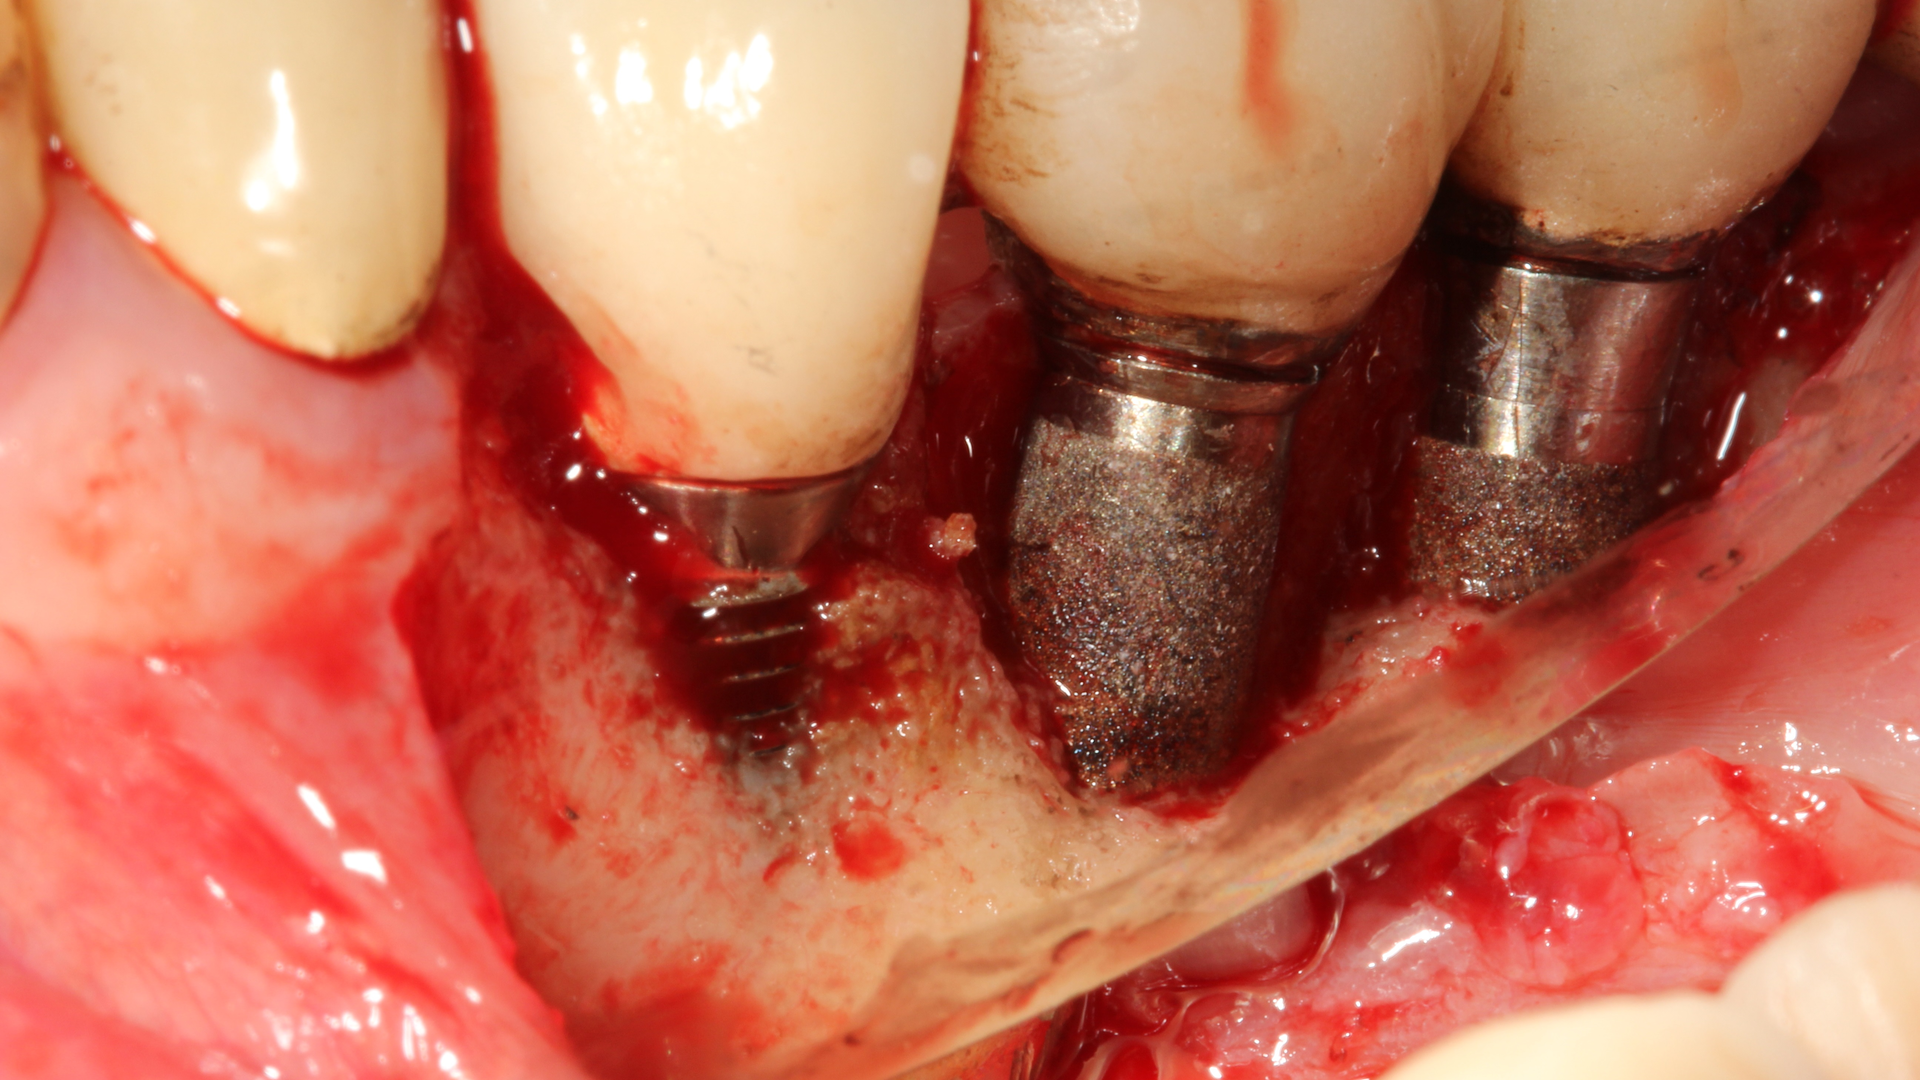

In a recent article discussing two case reports, Nd:YAG and 9.3 micron CO2 lasers were used to detoxify the inner lining of soft tissue surrounding ailing dental implants prior to tissue grafting (figures 1 and 2).12 Lasers can ablate the soft tissue of this particulate (metal) material while killing some of the residual translocated/invasive bacteria, thereby facilitating soft- and hard-tissue healing.

This video demonstrates laser detoxification of the inner lining of the soft-tissue flap, approximating failed dental implant and showing titanium particles embedded into the soft tissue with sparks flying during ablation:

Both the Nd:YAG and 9.3 micron CO2 lasers can have an impact on enhancing soft-tissue healing. Their ability to ablate residual titanium and/or cement from the inner soft-tissue flap lining may help enable the ailing implant sites to successfully heal.